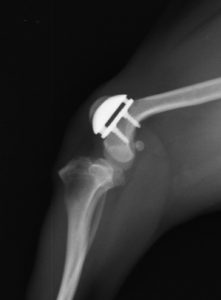

特殊な場合として、人工滑車溝置換術を行うことがあります。

慢性的なお皿の脱臼を長期的に放置していたことにより、関節軟骨がすでに無くなってしまっている場合、人工的な関節軟骨を設置することで なめらかな膝蓋骨の動きを取り戻すことができます。

チワワ2.5kg 人工滑車溝の設置